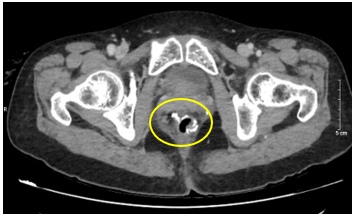

-        CT scanner ổ bụng :

Hình 2: Hình ảnh khối u trực tràng giữa qua chụp CLVT. Trực tràng giữa thành dày không đều quanh chu vi, chỗ dày nhất 17mm, trên đoạn dài 40mm, không rõ cấu trúc lớp, ngấm thuốc mạnh sau tiêm.